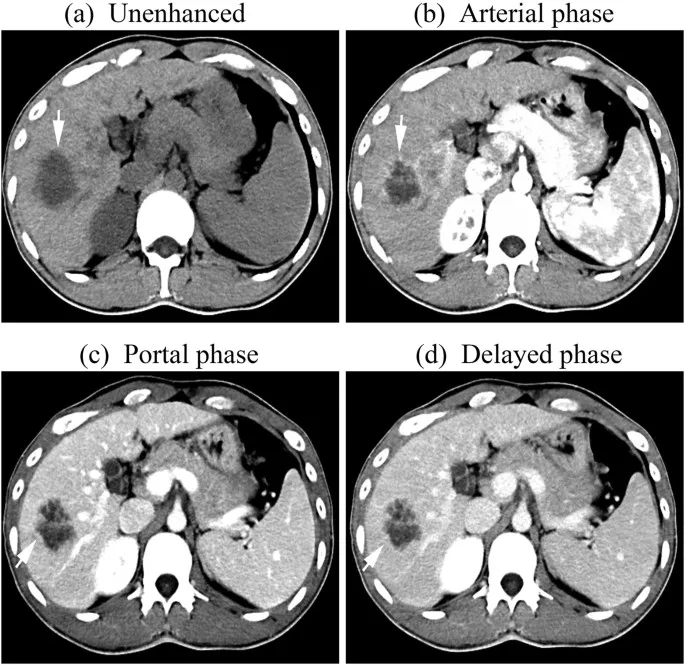

- ⭐ > The portal venous phase (60-90s) is crucial for most routine abdominal CTs, offering optimal solid organ and venous structure enhancement.